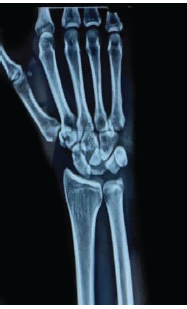

Neglected Isolated Lunate Dislocation in a Polytrauma Patient Presenting as Acute Carpal Tunnel Syndrome – A Case Report with Review of Literature

Warid Altaf , Amit Chaudhari , Parag Sancheti

………………………………p.159-163